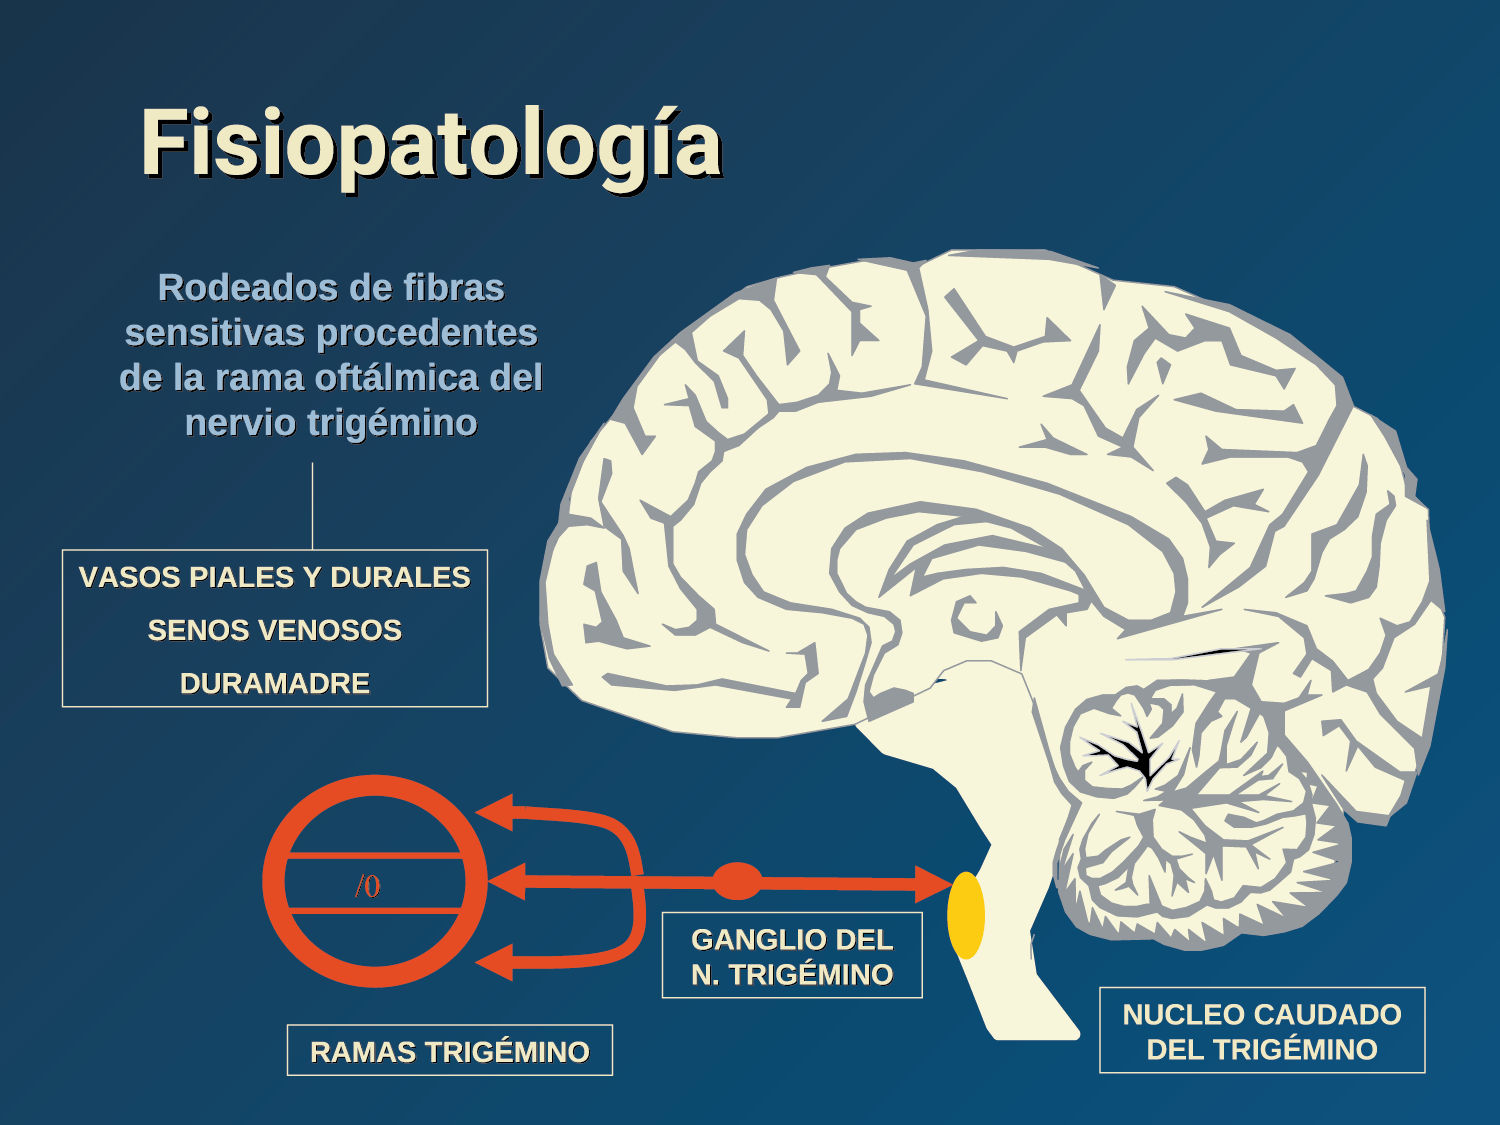

Todo lo mencionado contribuye al fenotipo del migrañoso y son vías que continuamente se están explorando para el desarrollo de nuevas terapias agudas y preventivas del dolor, más seguras y eficaces. Sin embargo, existe una controversia que gira en torno a dos cuestiones: la iniciación y el origen del dolor además de que todavía no se conoce el origen de los mecanismos neuronales que subyacen a la condición primaria en las personas susceptibles. Definitivamente la migraña implica la activación y sensibilización de las vías trigeminovasculares, así como el tronco cerebral y los núcleos diencefálicos(88). La vía aferente comienza en las aferentes vasculares nociceptivas de la duramadre que están para advertir, no para localizar. Su proyección al tálamo y la corteza y como se regula esta vía en cada nivel y por múltiples sistemas, ofrece la posibilidad de comprender los síntomas complejos y orientar las terapias. Los ataques comienzan como síntomas premonitorios, dificultad para concentrarse, bostezos, fluctuaciones del humor; y cambios homeostáticos, como la alimentación y el equilibrio de líquidos, que pueden incluir sensibilidades más generalizadas, como fotofobia y fonofobia. La fase premonitoria da paso a la fase de dolor con el sufrimiento acompañante y termina en una fase posdrómica de sentirse agotado por la experiencia. (Figura 1)

El aura de la migraña, al menos en su sentido clásico, tiene relación con la depresión cortical que se propaga por la corteza cerebral y participa como un actor paralelo cuando se producen las crisis. (Figura 2)

La fisiopatología de la migraña había surgido de una consideración histórica de los “humores” hasta mediados del siglo XX con la ahora desaparecida Teoría Vascular. Pero aún se podría decir que hay tres preguntas: ¿por qué, cómo y cuándo? Por qué: se acepta en gran medida que la migraña es una tendencia heredada del cerebro a perder el control de sus vías de acceso de impulsos. Cómo: la ahora clásica vía aferente nociceptiva vascular de la duramadre del trigémino ofrece una hoja de ruta del ataque. Cuándo: los ataques de migraña surgen debido a un trastorno del procesamiento sensorial del cerebro que probablemente sea cíclico, influenciado por la genética y el medio ambiente.

El dolor de cabeza asociado con un ataque de migraña, puede incluir la región frontal, temporal, parietal, occipital y cervical alta, es consecuencia de la activación del sistema trigeminovascular. (Figura 10)

La anatomía del sistema trigéminovascular ha sido bien descrita durante los últimos 70 años y esto ha ayudado a comprender la fisiopatología de la migraña y la distribución de su dolor. Se sabe que el cerebro es en gran parte insensible, pero un rico plexo de fibras nerviosas nociceptivas que se originan en el ganglio del trigémino inervan los vasos sanguí- neos de la piamadre, la aracnoides y la duramadre, incluidos el seno sagital superior y la arteria meníngea media, así como las grandes arterias cerebrales. (Figura 11) (23)

La inervación nociceptiva de la vasculatura intracraneal y las meninges incluye proyecciones axonales no mielinizadas (fibras C) y mielinizadas delgadas (fibras Aδ), principalmente a través de la división oftálmica (V1) del nervio trigémino, pero también, en menor medida, a través del nervio maxilar. (V2) y divisiones mandibulares (V3). También hay inervación neuronal de la duramadre desde los ganglios de la raíz dorsal cervical (24) (Figura 12).

Hay una proyección aferente central desde el ganglio del trigémino que ingresa a la médula caudal del tronco encefálico, a través del tracto del trigémino, que termina en el núcleo espinal del trigémino caudalis (TNC), así como la médula espinal cervical superior (C1–C2). (Figura 16)